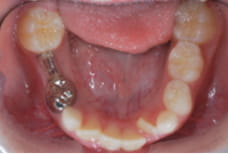

バンドループ / クラウンループ

永久歯が生えてくるまで、ワイヤーを使って永久歯の場所が狭くならないようにします。

(左:バンドループ / 右:クラウンループ)(上:バンドループ / 下:クラウンループ)